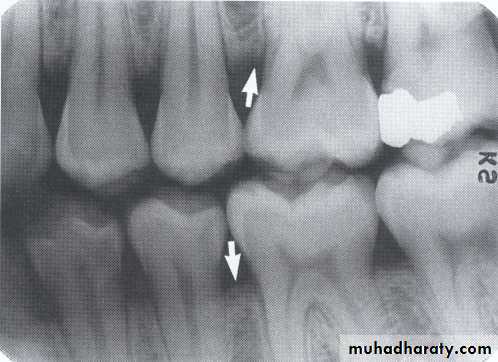

Dental radiographs provide an overview of the amount of bone present & indicate the pattern, distribution & severity of bone loss.

The bitewing radiograph is the view of choice for the evaluation of periodontal disease.

1. Horizontal bone loss:- When loss occurs on a plane that is parallel with a line drown.

2.Vertical bone loss:- when there is greater bone loss in one tooth than on the adjacent tooth, so the bone level is not parallel with a line joining the CEJ.